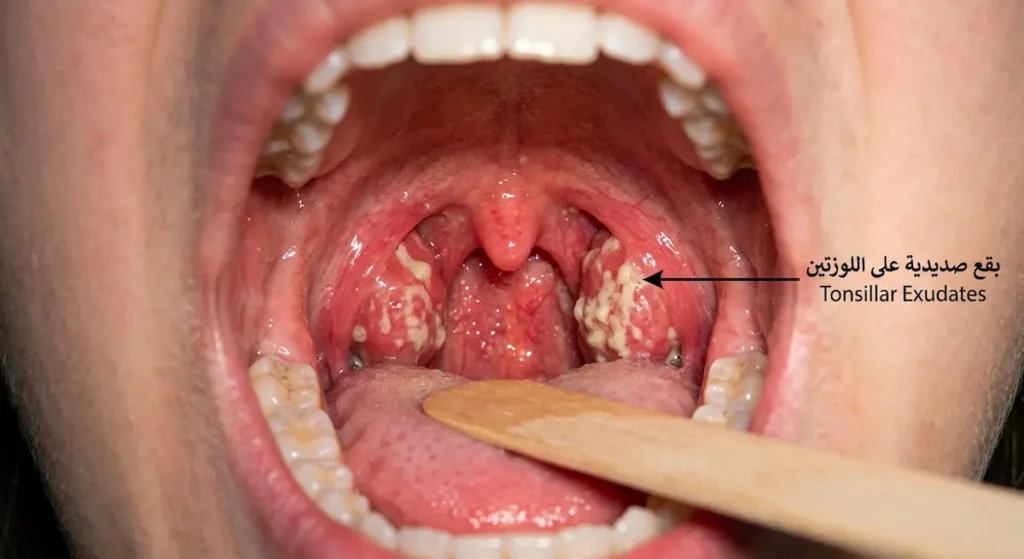

أول ما يلفت انتباه المريض هو ألم الحلق. يبدأ عادة كشعور بالجفاف أو “الخدش” في مؤخرة الحلق، ثم يتصاعد خلال ساعات إلى ألم حقيقي يزداد حدة مع كل محاولة للبلع. في النوع البكتيري، يكون الألم شديداً لدرجة أن بعض الأطفال يرفضون الأكل والشرب تماماً. عند فحص الحلق بالمرآة أو مصباح الهاتف، قد ترى احمراراً واضحاً في جدار البلعوم الخلفي مع تورم اللوزتين. وفي الحالات البكتيرية، تظهر بقع بيضاء أو صفراء صديدية (Tonsillar Exudates) على سطح اللوزتين، وتبدو كنقاط قيح واضحة.

| وجه المقارنة | التهاب البلعوم الفيروسي | التهاب البلعوم البكتيري (العقدي) |

| بقع صديدية على اللوزتين | نادرة | شائعة ومميزة |

- وجود إفرازات صديدية على اللوزتين (نقطة واحدة)

| وجود إفرازات صديدية على اللوزتين (Tonsillar Exudates) | +1 |

الإفرازات الصديدية على اللوزتين (Tonsillar Exudates)

التعريف: بقع بيضاء أو صفراء تظهر على سطح اللوزتين الملتهبتين، تتكون من خلايا ميتة وبكتيريا ومخاط. علامة مميزة للالتهاب البكتيري.